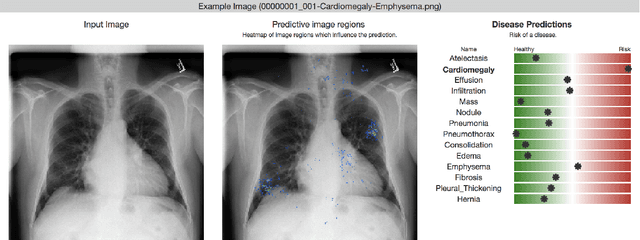

Deep learning has shown promise to augment radiologists and improve the standard of care globally. Two main issues that complicate deploying these systems are patient privacy and scaling to the global population. To deploy a system at scale with minimal computational cost while preserving privacy we present a web delivered (but locally run) system for diagnosing chest X-Rays. Code is delivered via a URL to a web browser (including cell phones) but the patient data remains on the users machine and all processing occurs locally. The system is designed to be used as a reference where a user can process an image to confirm or aid in their diagnosis. The system contains three main components: out-of-distribution detection, disease prediction, and prediction explanation. The system open source and freely available here: https://mlmed.org/tools/xray/